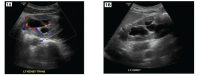

Figure 1.

Renal ultrasound left kidney transverse (A) and sagittal (B) views, showing moderate hydronephrosis with slight parenchymal thinning.